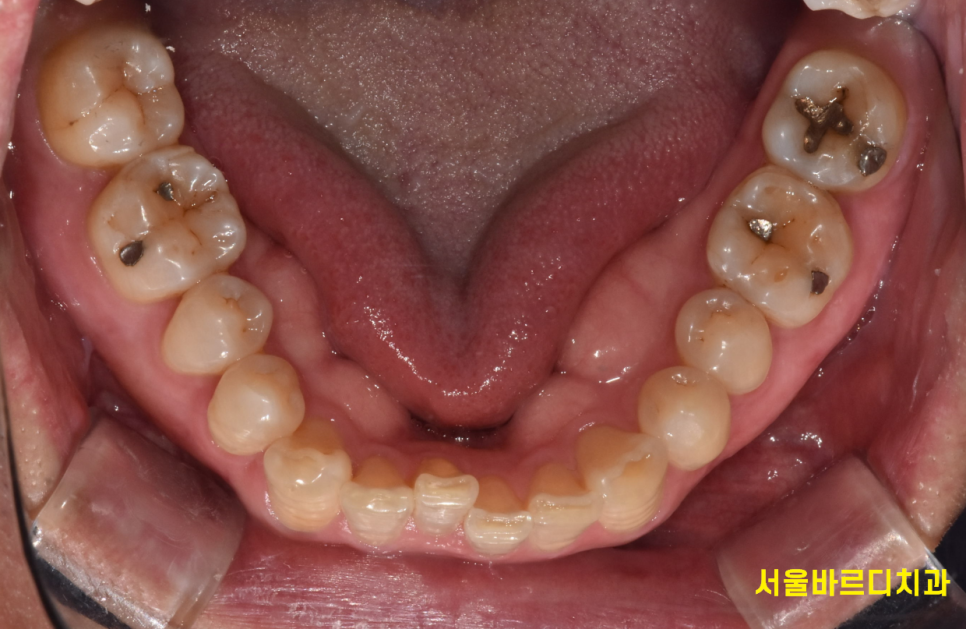

교합 상태, 치아 배열 상태를 확인하기 위해

5분할 포토라 불리는 구강 내 사진을 찍고

뽄도 뜹니다.

교정 모델을 만들기도 하며

이 과정에서 구강 스캐너가 동원되기도 합니다.

앞으로 교정을 통해 치아가 어떻게 움직일지 예측합니다.